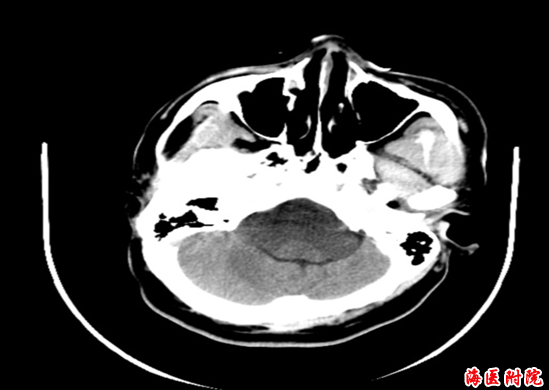

术前CT及CTA

术后CT